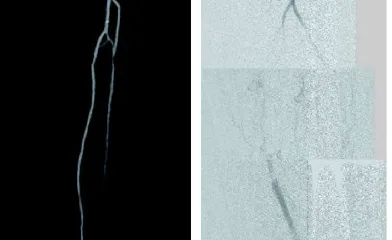

ケースレポート実際の臨床応用を通じて、製品への理解をさらに深めてください。 製品に関連するケースレポートをご覧ください並び替え昇順降順並び替え 昇順降順ポートフォリオ大動脈領域末梢血管領域ポートフォリオ 大動脈領域末梢血管領域関連製品ゴア® TAG® コンフォーマブル 胸部大動脈ステントグラフト アクティブコントロールシステムゴア® エクスクルーダー® IBEゴア® エクスクルーダー® コンフォーマブル AAAステントグラフト アクティブコントロールシステムゴア® バイアバーン® VBX バルーン拡張型ステントグラフト ゴア® バイアバーン® ステントグラフト関連製品 ゴア® TAG® コンフォーマブル 胸部大動脈ステントグラフト アクティブコントロールシステムゴア® エクスクルーダー® IBEゴア® エクスクルーダー® コンフォーマブル AAAステントグラフト アクティブコントロールシステムゴア® バイアバーン® VBX バルーン拡張型ステントグラフト ゴア® バイアバーン® ステントグラフト治療領域末期腎不全末梢血管疾患胸部大動脈疾患腹部大動脈瘤血管損傷治療領域 末期腎不全末梢血管疾患胸部大動脈疾患腹部大動脈瘤血管損傷 34 結果 Image 6 Fr 対応ゴア® バイアバーン® VBXバルーン拡張型ステントグラフトを用いた橈骨動脈アプローチによる腸骨動脈 EVTの一例 さらに詳しくImage AVGの人工血管延長術後に生じた再流出路狭窄症例に対してゴア® バイアバーン® ステントグラフトを挿入した一例 さらに詳しくImage DESによる左浅大腿動脈の慢性閉塞の治療後、コロナ禍の受診中断でステント内閉塞となり再来された一例 さらに詳しくImage SFAの長区域閉塞病変にゴア® バイアバーン® ステントグラフトを留置し、3年フォローした一例 さらに詳しくImage SFA入口部からの長区間超高度石灰化閉塞病変に対して外科的内膜摘除術との併用でゴア®バイアバーン® ステントグラフトを留置し、6か月フォローした一例 さらに詳しくImage SFA起始部のランディングに悩むCTO病変に対しゴア® バイアバーン® ステントグラフトを用いてEVTを完遂し、2年経過を観察した一例 さらに詳しくImage Shaggy Aortaを合併した遠位弓部大動脈瘤に対するTEVAR さらに詳しくImage ケースレポート:ゴア® TAG® コンフォーマブル 胸部大動脈ステントグラフト アクティブコントロールシステム さらに詳しくImage ケースレポート:ゴア® エクスクルーダー® IBE さらに詳しくImage ケースレポート:ゴア® バイアバーン® VBX バルーン拡張型ステントグラフト さらに詳しくImage ケースレポート:ゴア® バイアバーン® ステントグラフト さらに詳しくImage ケースレポート:外傷性胸部大動脈損傷に対するゴア® TAG® コンフォーマブル 胸部大動脈ステントグラフト アクティブコントロールシステムの有用性 さらに詳しくImage ゴア® TAG® コンフォーマブル 胸部大動脈ステントグラフト アクティブコントロールシステムの特徴および有用性 さらに詳しくImage ゴア® バイアバーン® ステントグラフトの使い所 –長期開存したISO症例– さらに詳しくImage ゴア® バイアバーン® ステントグラフトを人工血管内シャント静脈側吻合部狭窄のリコイルに対して用いた症例 さらに詳しく さらに表示 トップ